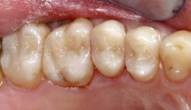

Case 1

missing

Decayed Tooth

After Composite Filling